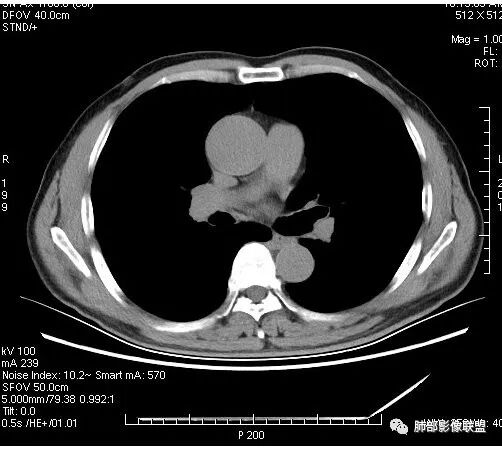

有空泡征,实性部分密度均匀?强化均匀?

内部血管怎么样?

看着内部强化比较散呢,结核一般不是周围强化,肉芽肿组织,内部如果是坏死物也会强化吗

傅昌瑜:

晨读:男,67岁,体检发现右肺结节。近圆形,支气管及伴行血管进入结节,进入结节后支气管堵塞,血管走形尚自然,结节内血管边缘凹凸不平。远端边缘见毛刺(软毛刺?)及分叶。见胸膜牵拉。实变中见空洞。整体膨胀感不明显。考虑炎性肉芽肿可能,隐球菌病可能性大。注意鉴别鳞癌、结核。

虽然良恶性征象都有,但是这个病灶增强后坏死比较明显,如果是恶性:腺癌这样大小的结节坏死很少见,只有低分化腺癌可以坏死,但是低分化腺癌这种大小一般会有周围转移表现(叶间胸膜结节,癌淋或者淋巴结明显肿大),如果是鳞癌,收缩力,坏死情况以及没有支气管截断都不太支持,而且结节远端有几个小结节样改变,大家可能认为是血管,但我觉得应该是卫星灶。所以觉得隐球可能较大。壁胸膜的牵拉线也没有引起胸膜凹陷,比较纤细,至于病理中的丝状物不一定是真菌菌丝。

我觉得穿过病灶的血管挺有特点,自然,没被吃掉,如果小细胞或者淋巴瘤可以,但后2个病有空洞不符

这个大部分边缘稍微偏平直一点,血管走行非常自然,包括里面的空泡征样的,影子很干净,边界很光滑,都是些炎性特点。

4.病灶轻到中度强化。病灶内血管走行较完好,病灶旁血管局部显示粗大。